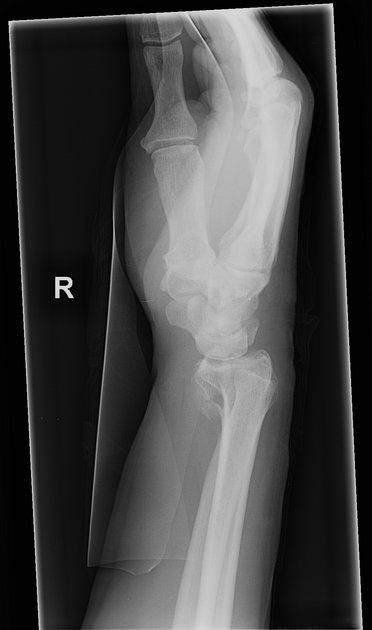

colles’ fracture

26

New cards

smith’s fracture